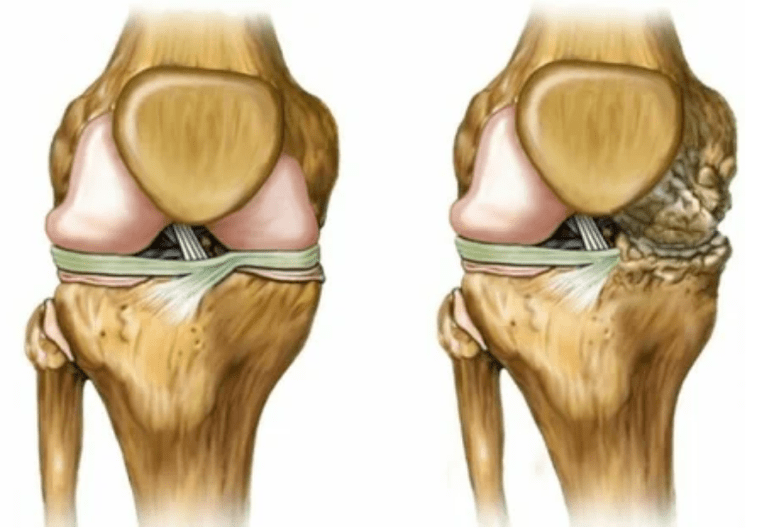

Die Arthrose des Gelenks wird über lange Zeit entwickelt, beeinflusst zunächst nur den hyalinen Knorpel und verbreitet sich dann auf die Knochen, umfasst die Synovialschicht, die Muskeln und die gesamte Gelenkkapsel. Im ersten oder frühen Stadium der Arthrose manifestiert sich die Läsion leicht: kleine Schmerzen nach harter Arbeit, Schwellung, Rötung der Haut. Aufgrund der Ignorierung der unangenehmen Empfindungen ist das Gelenk deformiert, entzündet, starken Schmerzen, und sein Höhepunkt fällt am Morgen. Die Krankheit ist durch das Verschwinden von Schmerzen nach der Entwicklung der Artikulation gekennzeichnet. Wenn nicht, verliert eine Person die Mobilität des Gelenks vollständig.

- Reduzierung der Lücke in der gemeinsamen Lücke, die im Bild bemerkenswert wird. Das Vergewaltigungsstadium wird vom Diagnose-Tantnologen bestimmt. Der Patient spürt die Komplexität oder Unfähigkeit, das Glied vollständig zu begradigen und zu falten.

- Gelenkverformung, Knorpel erhält eine unregelmäßige Form, provokative Krümmung;

Gliedmaßenverformungen. Es erscheint in einer unachtsamen Art der Krankheit und zeigt die vollständige Zerstörung des Knorpelgewebes und das Erscheinungsbild von Osteophyten an. In diesem Zustand nimmt der Druck auf die Gelenke im oberen und unteren Teil zu, aus dem die Krümmung das gesamte Glied beeinflussen kann.

Um eine Diagnose zu stellen, untersuchen Rheumatologen die Beschwerden des Patienten und verschreiben eine X -Ray -Untersuchung. Meistens wird die Radiographie in 2 Projektionen verwendet. Der Arzt analysiert das Vorhandensein von Verteilungsstörungen in den Hyalinenknorpel- und Knochenverbindungen. Wenn die Gelenkspalte verringert wird, die Knochen verzögert oder abgeflacht sind, gibt es zystische Formationen auf der Knorpeloberfläche, Osteophyten sind offensichtliche Anzeichen einer Arthrose. Während der Inspektion zeigt die Arthrose auf die Instabilität der Artikulation an: die Achse der Gliedmaßen und die Subluxation wird verändert.